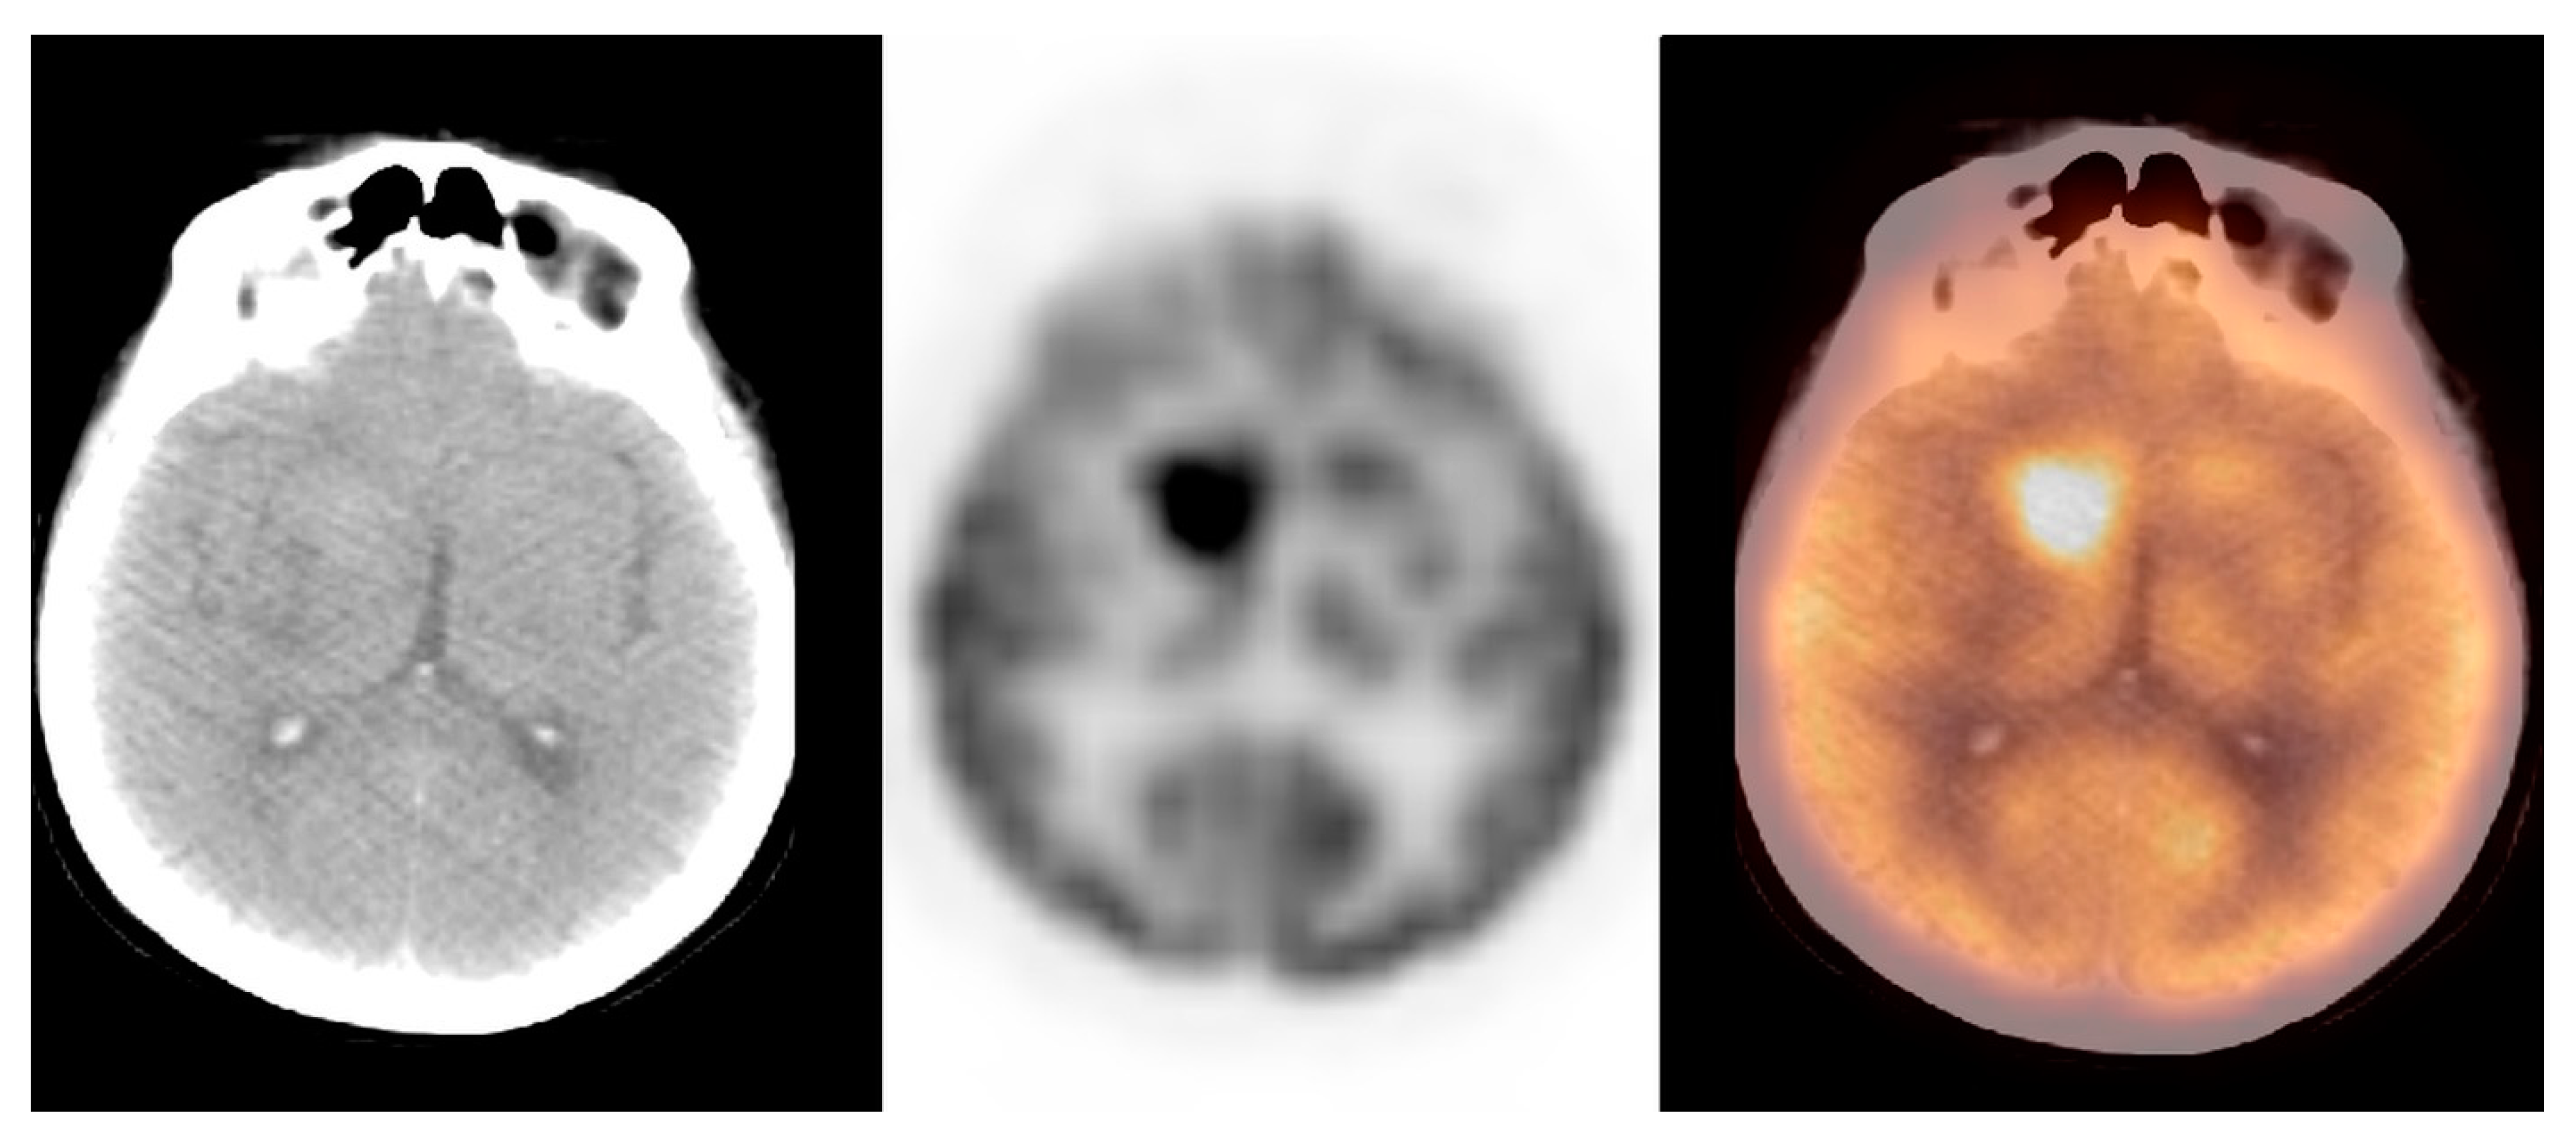

3.2.4. Metastatic Foci

| Metastatic foci | 12.4 ± 5.6 | 12.0 | 4.0–33.0 | [11.3; 13.5] |